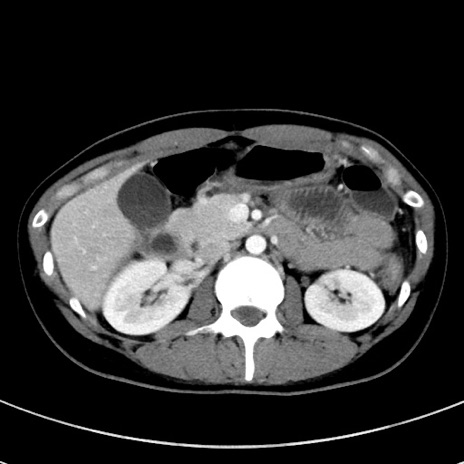

症例17(横断像)

【症例】20歳代女性

【主訴】嘔吐、下腹部痛

【現病歴】昨日夕食後に嘔吐し下腹部痛が出現。本日になっても嘔吐持続し改善しないため来院。

【身体所見】意識清明、BT 37.2℃、BP 108/67mmHg、腹部:平坦、やや硬、下腹部正中から右にかけて圧痛あり、反跳痛軽度あり、tapping pain(+)。

【データ】WBC 13600、CRP 14.94